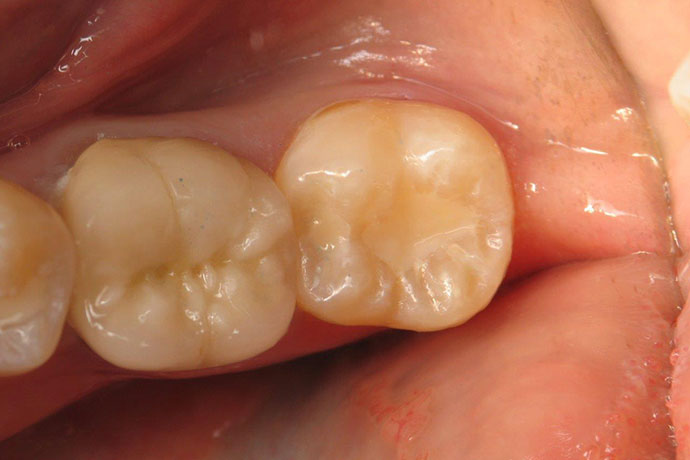

Crowns

After